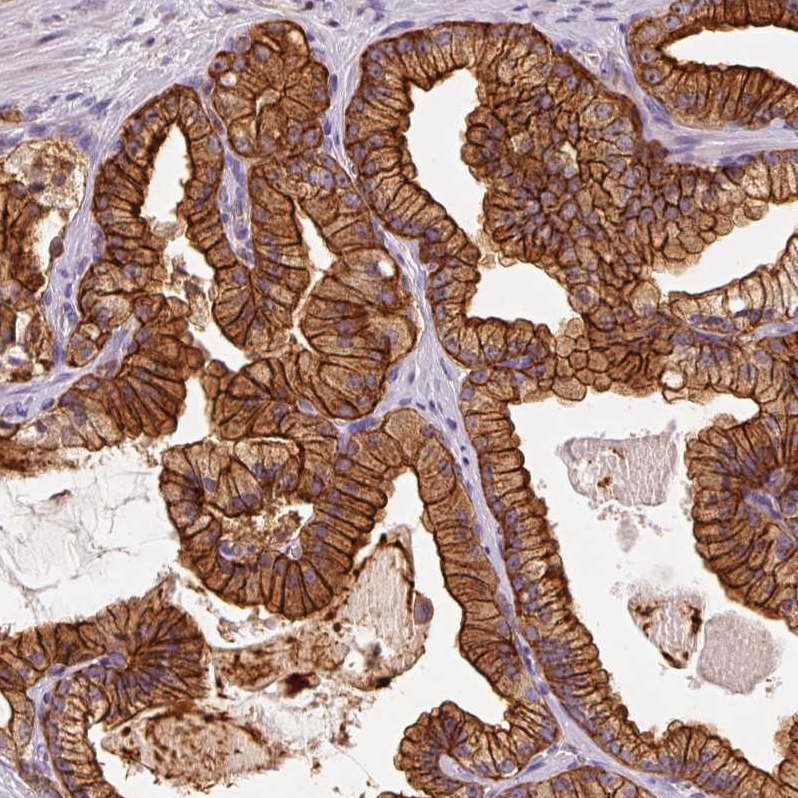

Immunohistochemical staining of human prostate cancer shows strong membranous and cytoplasmic positivity in tumor cells.